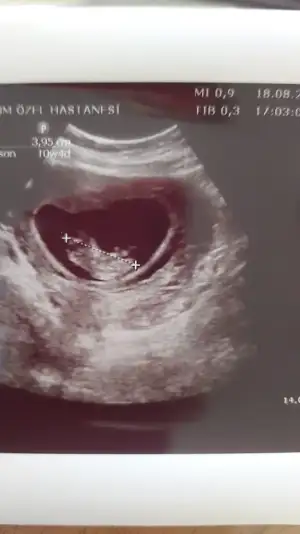

Bize de bakabilir misiniz 12 haftalık şimdiden teşekkürler ❤️

• IMG-20210823-WA0001.webp

IMG-20210823-WA0001.webp

44,2 KB · Görüntüleme: 88